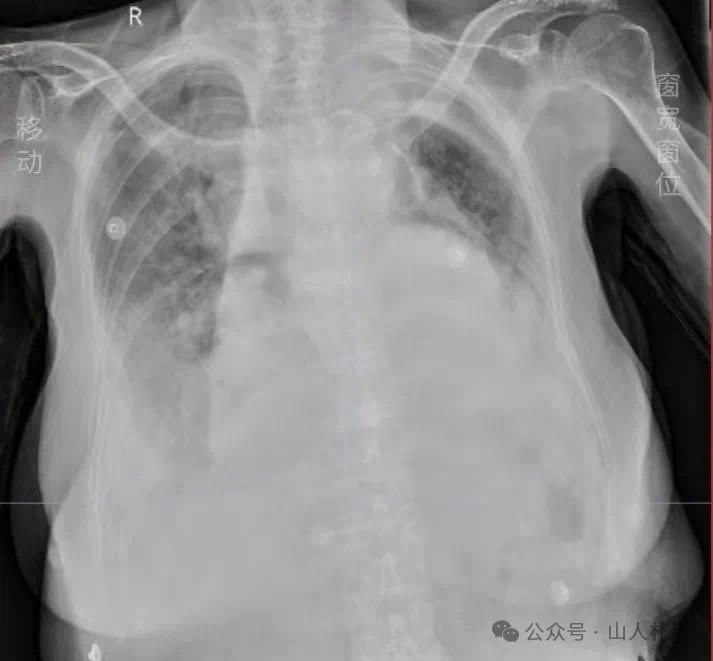

关于这次抢救,有的医师认为是急性左心衰发作、有的医师认为是胸腔积液压迫、有的考虑是肺部感染加重所致,而我始终认为,罪在麻黄、芥子,患者10余年前即有食道恶性肿瘤病史,手术切除了部分食道及胃,长期营养状态差,正气极虚,麻黄芥子解表后大汗出,肺气难存。这次抢救之后虽然患者没有发热,但考虑炎症指标的升高,遵从指示用了抗感染药物,患者出现了上吐下泻,甚至有完谷不化之象,脉也见结象。中药只能保胃气、救肾气,见效一般,难以调治,09-09复查胸片较前再次加重。